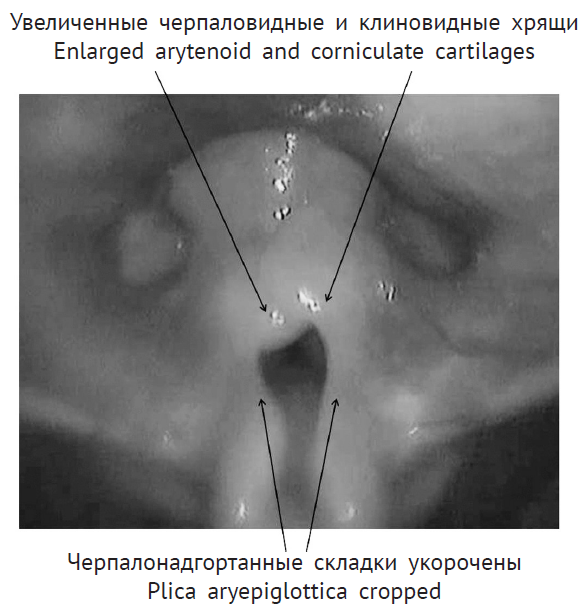

При назофаринголарингоскопии выявлены признаки ларингомаляции 2-го типа: надгортанник свернут в виде желоба, черпалонадгортанные складки укорочены, увеличенные черпаловидные и клиновидные хрящи выдвинуты вперед и прикрывают голосовой отдел гортани, подголосовой отдел не обозрим. Однако просвет гортани для дыхания в динамике сохранен, частичный коллапс преддверия гортани на вдохе за счет сближения краев надгортанника и пролабирования клиновидных хрящей. На рентгенограмме шеи в боковой проекции просвет подголосового отдела гортани и трахеи прослеживается на всем протяжении, не изменен (рис. 2). Кислотно-основное состояние крови — насыщение капиллярной крови кислородом 95,6 %

Рис. 2. Рентгенограмма органов шеи в боковой проекции